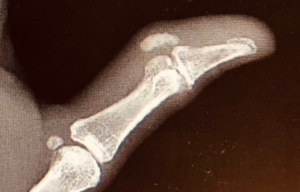

Our latest case report from Brady Pregerson, MD, featuresa woman in her mid-60s with a history of Hashimoto’s thyroiditis treated with levothyroxine presenting to the hospital with 4-5 days of pain, swelling and redness on her left thumb.

Published: October 16th 2023 | Updated: